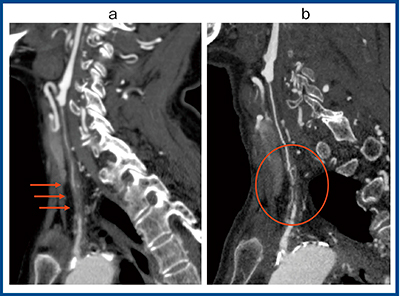

図7は左総頸動脈の高度狭窄の症例で,ADCT(a)では縦に長い血栓(→)があり,ほぼ完全閉塞しているように見えるが,Aquilion Precision(b)によるフォローアップでは,閉塞しているわけではなく,内部に細い側副血行路が発達して連続性があることが確認できた(○)。冠状断方向からの拡大画像(図8)でも,Aquilion Precision(b)では血管内部に順行性の血流が認められ,完全閉塞ではないことが診断できた。

図7 左総頸動脈の高度狭窄の比較画像

a:ADCT b:Aquilion Precision

図8 図7と同一症例の冠状断拡大画像